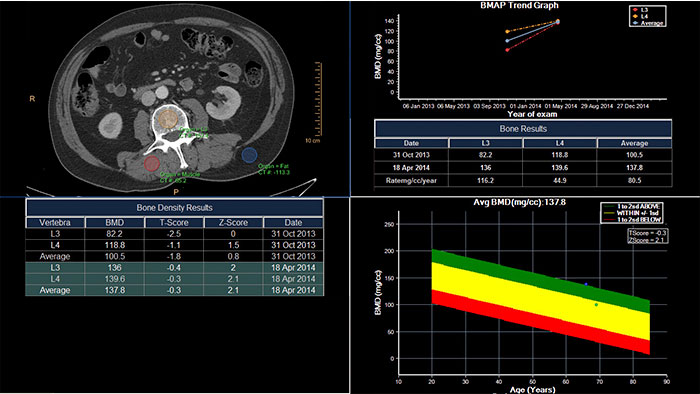

Track degenerative and metabolic bone disease

CT Bone Mineral Analysis (BMA) provides quantitative CT information to measure a patient's bone density, helping the physician assess the patient's risk of osteoporosis. CT BMA provides results without the need of a reference phantom.